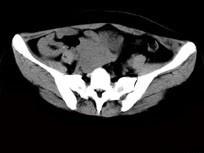

问题 女,24岁,近月余感尿频明显,CT检查如图,最可能诊断为 ( )

选项 A、盆腔纤维瘤 B、卵巢囊肿 C、子宫肌瘤 D、卵巢癌 E、膀胱癌

答案 A